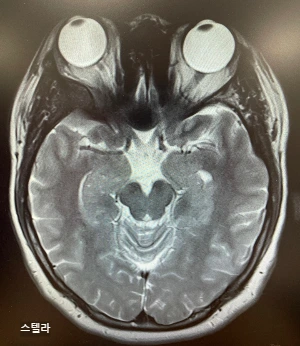

수술 전

수술 직후

교수님은 수술 전 후 MRI 사진을 비교해 주셨다.

사진을 보고 있자니 나도 모르게 눈물이 났다.